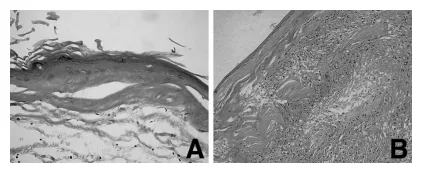

组织学检查显示囊肿与小脑实质分界清晰,未见侵袭性生长。囊壁内衬扁平鳞状上皮,无不典型性,上皮下纤维组织高度玻璃样变。囊腔内充满大量角化物质,未见未成熟神经组织等其他成分(图5A)。部分囊壁可见异物反应和淋巴细胞浸润(图5B)。患者术后恢复平稳,出院时无神经功能缺损。